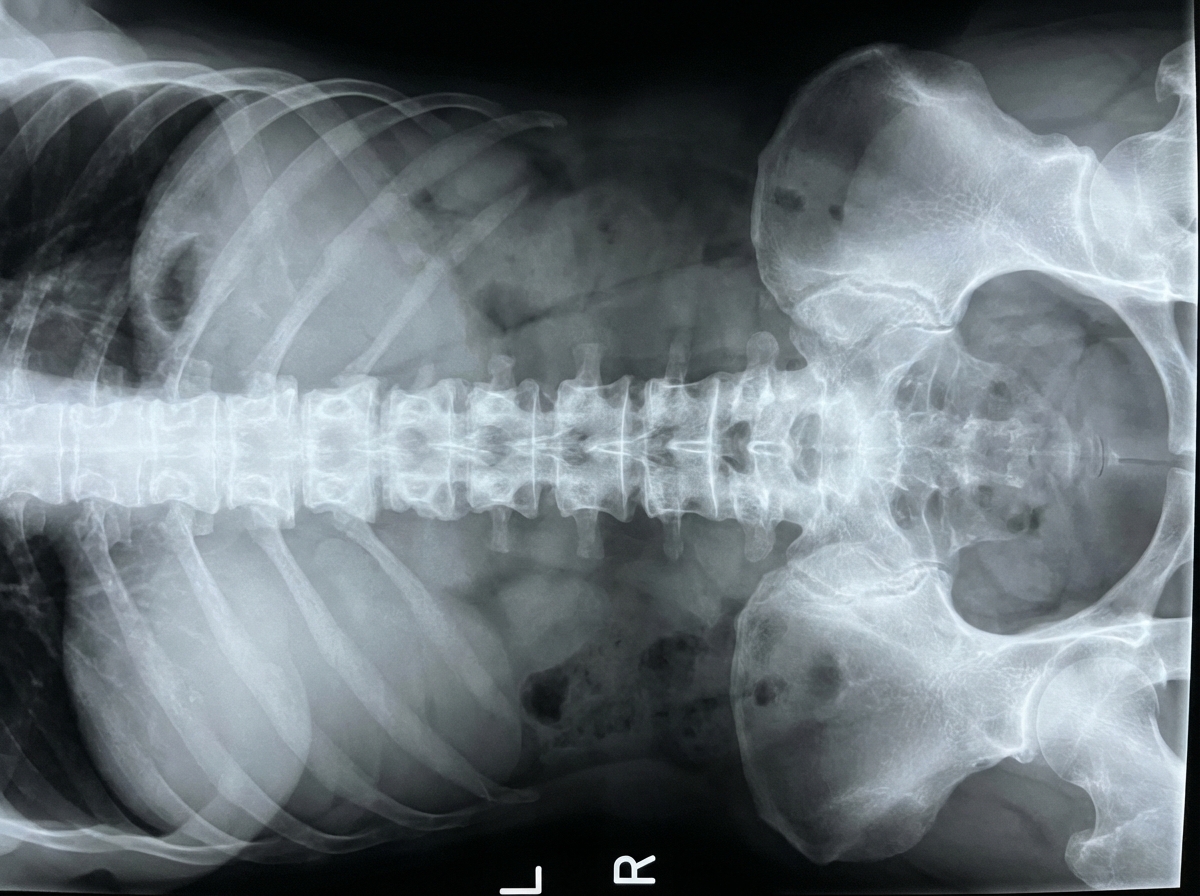

A 32-year-old man presents to the clinic with a dull low back pain radiating to the buttocks. He first noted it about 2 years ago and it has progressed since then. He notes that it is worse in the morning and improves later in the day after physical activity. The patient also reports morning stiffness lasting up to 30 minutes and blurred vision, which started about 7 months ago. The patient's vital signs include: blood pressure 130/80 mm Hg, heart rate 88/min, respiratory rate 16/min, and temperature 36.8°C (98.2°F). Physical examination reveals tenderness over the sacroiliac joints and limitation of the lumbar spine movements in the sagittal plane. The patient's X-ray is shown in the picture below. Which of the following HLA variants is associated with this patient's condition?